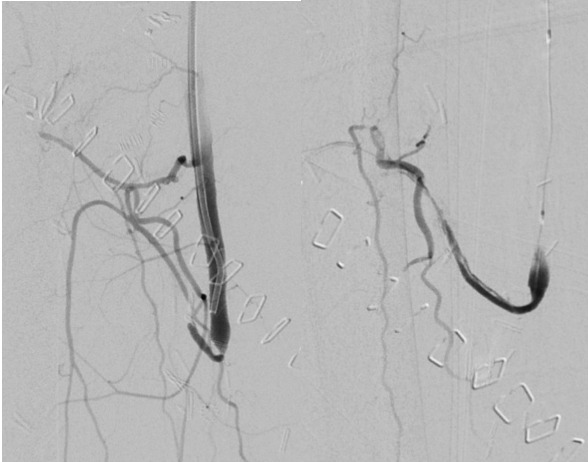

The patient started therapeutic enoxaparin and vascular surgical opinion was sought regarding options for flap salvage if it were to become necessary. Seven days postoperatively, the flap developed signs of arterial insufficiency (Figure 1).

Therapeutic enoxaparin was given, and radiologically guided catheter-directed thrombolysis commenced. Angiography via a retrograde left common femoral approach demonstrated extensive thrombus in the profunda artery proximal to the anastomosis over a length of 4 cm. The wire was passed beyond and a PROGREAT micro catheter run showed patent vessels in part of the flap. Attempts were made to clear the thrombus using 50,000 units of pulse spray urokinase through a small balloon catheter. Angioplasty using a 2 mm balloon was also performed proximally within the flap artery. Despite this, there was minimal restoration of angiographic flow yet significant clinical improvement of the flap was noted with re-establishment of an arterial Doppler signal.